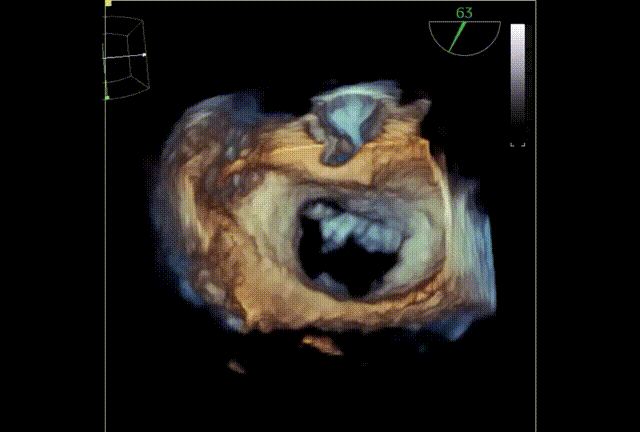

术后TEE显示二尖瓣双孔化形成,瓣膜夹稳定